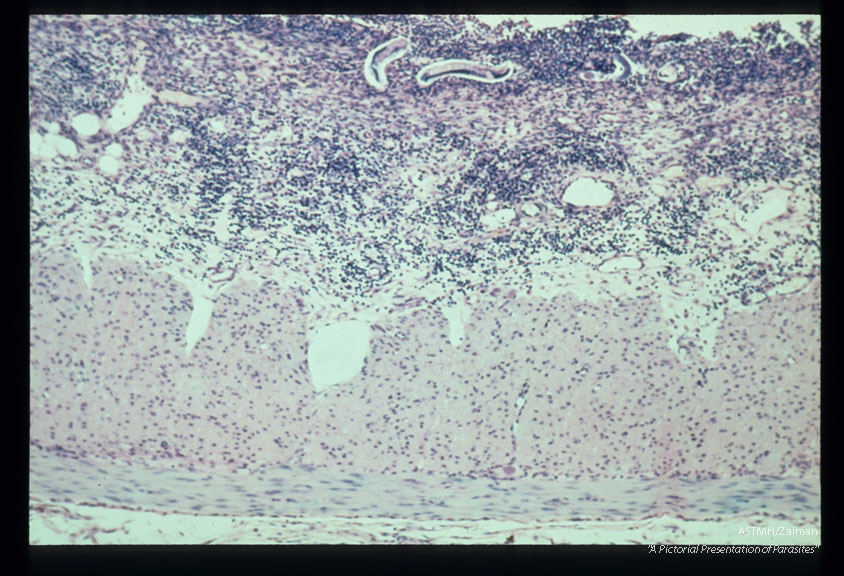

Duodenal ulcer induced by experimental infection of Erythrocebus patas.

Strongyloides stercoralis

Description: Duodenal ulcer induced by experimental infection of Erythrocebus patas.